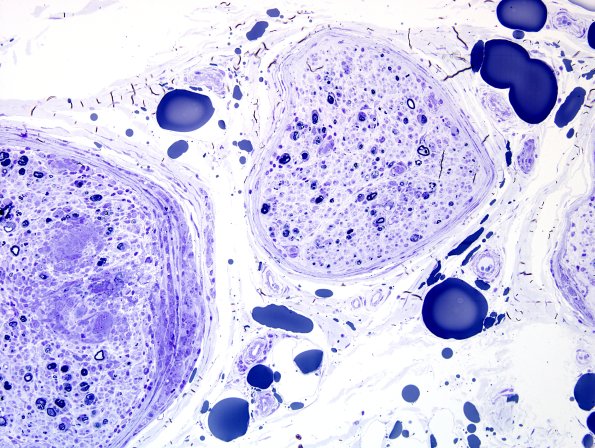

1E2A,B A low magnification image shows granulomatous involvement of the left fascicle involving both endoneurium and perineurium. The right fascicle is quite pale with marked axon loss and no granulomata, at least at that level. (Plastic sections)